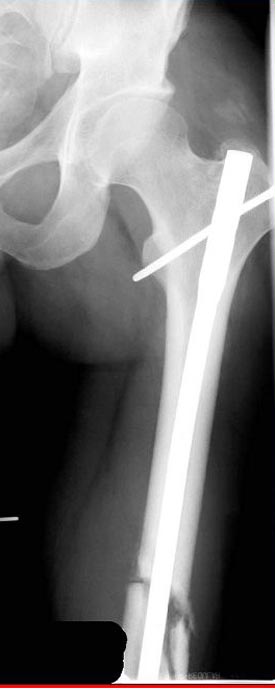

Лечение бедра - ургентное оперативное лечение антеградным с минимально рассверливанием, фиксацией с минимальным диаметром штифта и плюс irrigation and debridment и с закрытием поперечной до 10 см раны на уровне перелома в день поступления.

Снимки представлены: 1 мес; 3 мес; 1 год; 2 года, предоперационные и ротационная КТ грамма

Из трех вариантов:

Рассверливание с заменой более большого диаметра штифтом,

Остеотомия с фиксацией пластиной+костная пластика,

Аппарат Илизарова= Taylor spatial frame

Гвоздь для ротационных смещениц был бы идеальнымимплантом, после коррекции есть возможность блокировать, но из-за укорочения метод оставил на последнее место. Есть метод Сhaplan лечения ложных суставов бедра, где необходимость bone graft, накладывается феморальный дистрактор и после удаления штифта - рассверливание, через проксимальный канал вводят костный графт в место ложного сустава под рентген контролем, потом вводят штифт, кстати, само рассверливание дейстивует как стимулятор - активизирует восстановительный процесс.

Обычный мой первый выбор - вариант с пластиной, - учитывая бывшую инфекцию, открытую травму, посчитал метод менее приемливым.

Операцию провели в два этапа, сперва удалили штифт, рассверливание римером на пару мм большего диаметра, определение чувствительности на анаэробную и аэробную культуру (где исследования показали негативный результат чувствительности), через дней десять - начали аппаратную фиксацию.